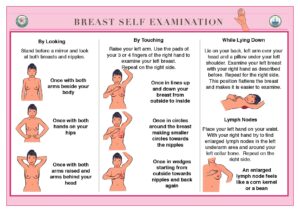

Self Breast examination once a month helps early diagnosis of breast lumps. An early diagnosis of breast cancer can result in complete cure. Regular breast cancer screening, such as mammograms and ultrasound breast, can help detect breast cancer early when it is more treatable. Increased awareness about breast cancer and early detection have contributed to improved outcomes.